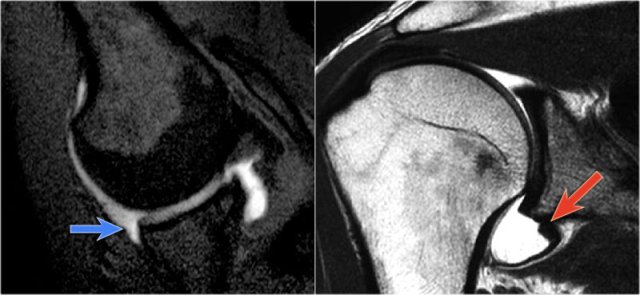

The MR-images are of a patient who had undergone both an anterior aswell as a posterior dislocation.

This resulted in both a Hill-Sachs impression fracture on the posterior aspect of the humeral head (blue arrow) and an impression fracture on the anterior aspect as a result of posterior dislocation (red arrow).